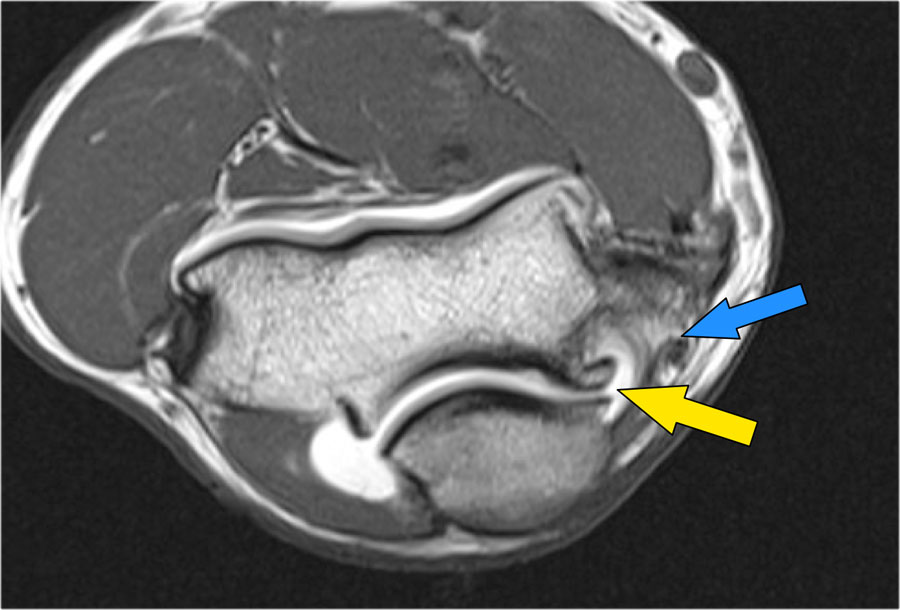

- Nếu bạn nhìn vào mỏm trên lồi cầu trong, bạn sẽ nhận thấy bó sau như một cấu trúc mỏng (mũi tên xanh).

- Notice the ulnar nerve sitting in the cubital tunnel.

- The posterior bundle forms the floor of the cubital tunnel.

- A retinaculum covers the cubital tunnel.

- Lưu ý rằng bó trước dày hơn nhiều (mũi tên trắng).

- Bạn có thể thấy sự khác biệt giữa dây chằng trước và dây chằng sau mặc dù chúng tạo thành một dây chằng duy nhất.

- Khi đi về phía xa, chúng ta sẽ thấy chúng hợp nhất lại để bám vào củ sublime.